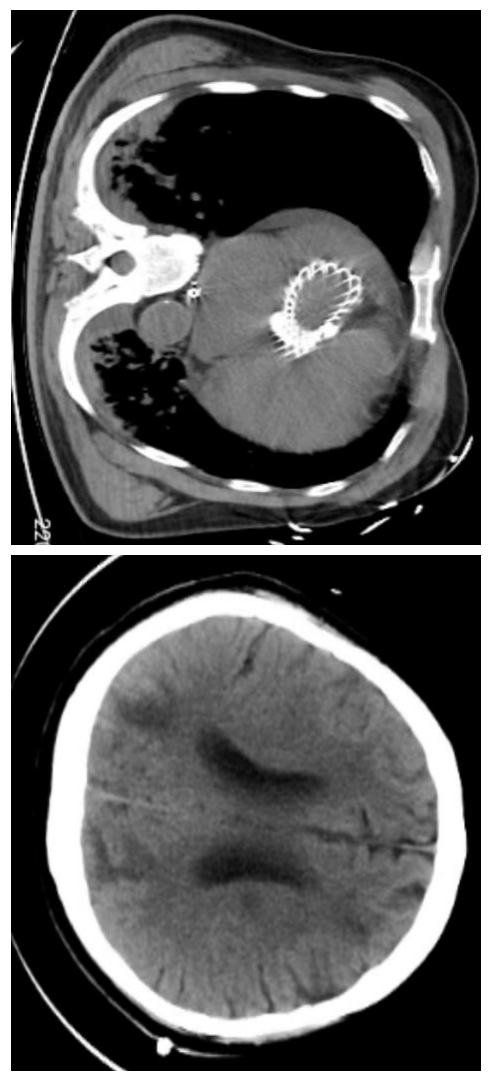

1 资料与方法患者男,78岁,既往有高血压病史10余年,有主动脉瓣狭窄病史,未治疗。2023-10-02 19:00患者无明显诱因下在家中出现呼吸困难,无胸痛,无背痛,21:00患者由120车送至本院抢救中心。来院时患者神志模糊,呼吸急促,SPO2 34%,即予气管插管,21:06患者出现心脏骤停,立即予心肺复苏,21:30启动ECMO团队。22:04 ECMO机器顺利运转。查体:血压82/60 mmHg,心率87次/min,呼吸28次/min,血氧饱和度100%,体温36.3℃。经口气管插管接呼吸机,ECMO转速3 100 r/min,流量3.1 L/min。左侧瞳孔直径1.0 mm,对光反射消失,右侧瞳孔直径1.0 mm,对光反射消失,心音微弱,心律齐,两肺呼吸音清,未闻及干湿性啰音,腹平软,压痛、反跳痛无法配合,肝脾肋下未及,双下肢无浮肿。双下肢ECMO管路留置在位。抢救室辅助检查结果如下:2023-10-02血常规+CRP:WBC 17.5×109/L,Hb175 g/L,PLT 204×109/L,CRP 4.99 mg/L。血生化未见明显异常。cTnT 0.031 μg/L,D二聚体824 ng/mL,BNP 3355.8 pg/mL。血气分析:pH 6.788,PCO2 67 mmHg(1 mmHg=0.133 kPa),PO2 59.8 mmHg,钾3.7 mmol/L,钠136.0 mmol/L,乳酸16.0 mmol/L。肌钙蛋白T 0.031 μg/L,床边心超:左室肥厚,左房增大,主动脉瓣钙化合并重度狭窄(最大开放面积约0.31 cm2),心包少量积液。心电图:加速的室性逸博心律,ST-T改变(V1-V4导联ST段呈水平抬高,I、V5、V6导联ST段呈水平型、下斜型压低0.05~0.5 mV)。当天患者转入ICU。2023-10-07患者出现无尿,予CRRT替代治疗。经院内外专家会诊后考虑患者本次心脏骤停原因为主动脉瓣重度狭窄,故于2023-10-08全麻下行“单根导管的冠脉造影+经导管主动脉瓣置入术(TAVR)”,术中见左主干、左回旋支无狭窄,左前降支中段85%狭窄,远段50%狭窄,主动脉瓣重度狭窄,置入启明26(瓣口)×50(支架长度)mm自膨式瓣膜输送系统,手术过程顺利。术后复查心超,EF45%,10.9撤离ECMO。完善CT(见图 1、图 2)。2023-10-12予气管切开。术后患者出现少量瓣周漏,同时存在胆囊炎、肺部感染、链球菌性败血症、贫血、低蛋白血症、血小板减少症,在补充红细胞、血浆、白蛋白、人免疫球蛋白的基础上,予积极抗感染、抗凝、抗血小板等药物治疗、康复治疗,2023-11-17予停CRRT。2023-11-22予顺利脱机。2023-11-25患者神志由模糊转清醒。2023-12-15患者转入心内科。2023-12-29予局麻下行“药物洗脱冠状动脉支架置入术(PCI)”,术中所见同前,手术过程顺利。术后患者生命体征稳定,后转至康复病房行康复治疗。2024-01-30患者康复出院。

| 图 1 10月10日患者术后肺部及头颅CT |